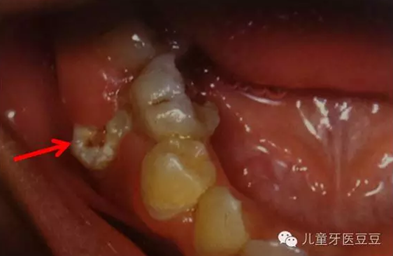

0IG~(~2ELPN~$0HI(Q[)2$6.png

乳牙反復根尖發(fā)炎導致繼承恒牙發(fā)育不良